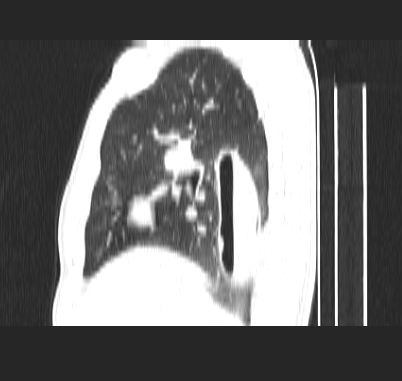

标题: CT19170:男 24岁,胸部外伤一周行CT检查 [打印本页]

男 24岁,胸部外伤一周行ct检查 未传纵隔窗

考虑右肺下叶纵隔胸膜下液气囊肿。

考虑外伤肺撕裂致右肺下叶纵隔胸膜下液气囊肿。

右肺下叶纵隔胸膜下液气囊肿,考虑肺囊肿?肺隔离症?